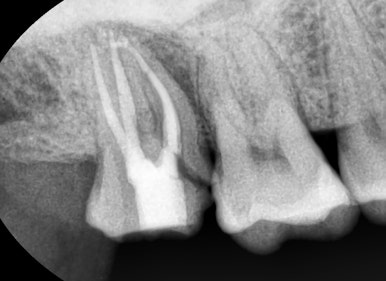

신경치료를 하고 크라운을 하지 않고 몇년간 방치하여 부러진 치아

어금니 신경치료는 아주 특이한 경우를 제외하고는 반드시 크라운을 하셔야 하며

크라운을 하셔도 뿌리가 부러질 만큼 신경치료한 치아는 약해져 있으니

그 신경치료한 치아로 씹으시려면 반드시 크라운을 하셔야 합니다.

오래된 신경치료한 치아의 뿌리가 부러져서 환자가 악취가 나고 아프다고 방문 → 발치

만약 신경치료한 치아를 씌우지 않아 뿌리부분이 두 동강나거나 파절된다면 살릴 수 없어

발치하는 경우가 많게 됩니다.